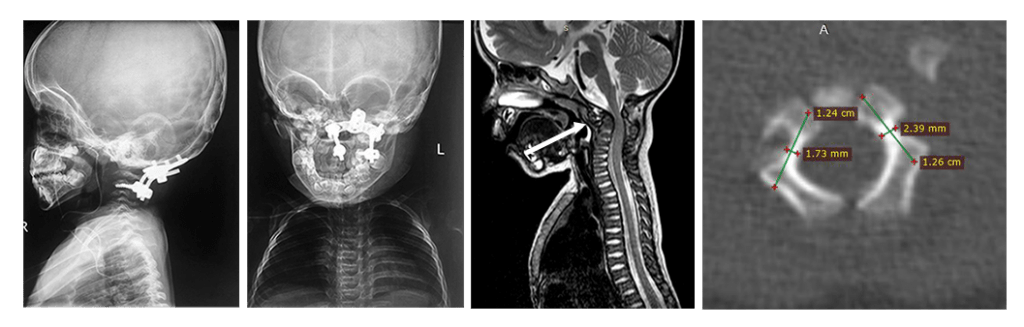

На снимках: ребенок 3 лет со спондилоэпиметафизарной дисплазией и тетрапрегией, имеется нестабильность в области краниоцервикального перехода с сдавлением спинного мозга. Стрелкой обозначен смещенный вперед атлант. Очень маленькие размеры позвонков. Проведена фиксация «второй шейный позвонок – затылок», костная пластика. Смещение атланта и нестабильность устранены. Восстановление движений в конечностях после операции. Ребенок самостоятельно начал ходить.